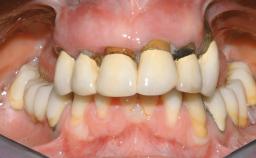

Immediate Loading of Eight Implants in the Maxilla and Six Implants in the Mandible and Final Restoration with Three-Unit and Four-Unit FDPs

Extensive scientific evidence has confirmed that immediately loaded implants with fixed full-arch provisional restorations can osseointegrate with success rates similar to conventionally or delayed loaded implants. A number of immediate-provisionalization techniques for edentulous jaws have been described. Some protocols differ when it comes to prefabricated provisional templates versus complete denture conversion; intrasurgical impressions versus direct relining; and cemented versus screw-retained provisional restorations. In this context, complete-denture conversion has been proposed for either intrasurgical impressions or direct relining. Another possibility is the utilization of a prefabricated provisional to be adapted either in the mouth (by direct relining) or in the laboratory (on a working model obtained from an intrasurgical impression).

Defining Characteristics Fully edentulous upper jaw to be rehabilitated with an implant-borne fixed dental prosthesis

Loading Protocol Immediate

Retention Cemented, with prosthesis margin < 3mm submucosal Cemented, with prosthesis margin < 3mm submucosal